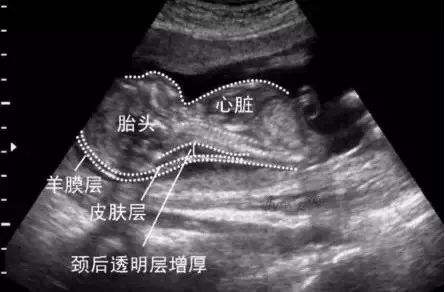

所谓NT,也就是胎儿颈后透明层扫描,它是一种筛查胎儿染色体和胎儿心脏结构异常的手段,也是孕期最早的排畸检查项目。

一般NT除了要检查胎宝宝颅骨是否发育正常(排除无脑儿)以外,最主要的还是要检查胎儿颈后透明层的厚度,然后通过测量胎儿颈后皮下液体(透明层)的厚度,可以检查出胎儿患有染色体异常(具体表现为胎儿出生以后智力低下、无生存及自理能力)的可能性。

前面说过NT检查主要是测量胎儿颈后透明层的厚度,如果该厚度低于3毫米(或者2.5毫米),说明胎宝宝患有异常的可能性很低,也可以说是正常的现象,产检通过,准妈妈无需过于担心。

而如果胎宝宝颈后透明层的厚度大于等于3毫米(还有些医院的标准是2.5毫米),则说明胎儿存在异常的可能性很大,简单来说就是宝宝有可能发育畸形。对于这种情况,医生一般会建议准妈妈做进一步检查。